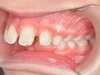

Chevauchement sévère. Traitement multibague sans extraction.

Avant

Après